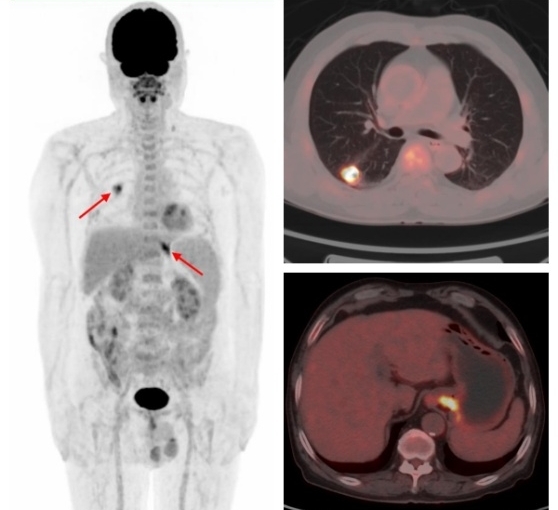

例1:中年男性,CT發(fā)現右肺上葉結節(jié),1.1cm×1.0cm,余未見異常,這時候患者初步分期應該是ⅠA期,屬于早期肺癌,可以行根治性手術。而PET/CT檢查示:肝臟、多發(fā)骨骼轉移,這時候分期直接跳到ⅣB期,屬于晚期肺癌,不適合手術,可以根據病理、基因檢測結果選擇合適的藥物治療或聯(lián)合治療方案,避免了無效的手術創(chuàng)傷。病理:浸潤性腺癌。

原發(fā)肺腺癌合并賁門腺癌